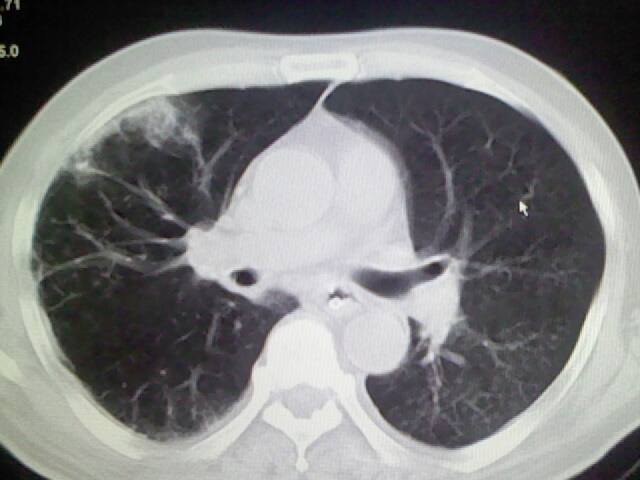

男,70岁,脑出血,长期卧床,左侧背部可触及肿块

考虑右肺及左肺下叶炎症。

右肺及左肺下叶炎症。

考虑右肺及左肺下叶慢性炎症。

右侧肺部见片状密度增高影,边缘模糊。考虑炎症。另食管壁增厚。

右肺上叶前段病呈楔形,其尖端指向肺门,考虑肺动脉栓塞可能性大.